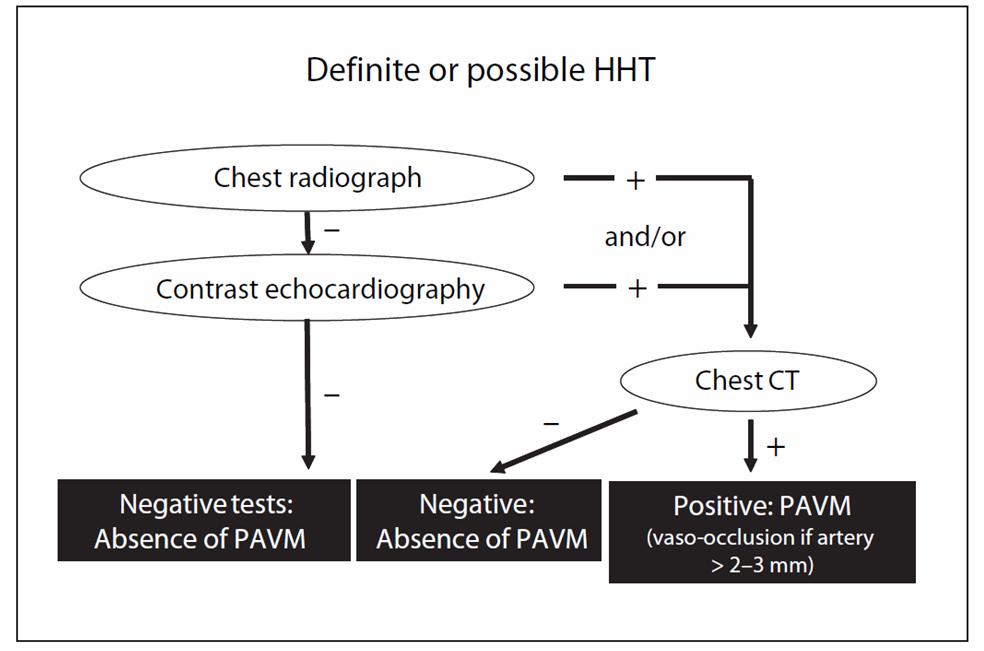

Finally, screening of PAVM is mandatory in all HHT patients according to international guideline 200914. Chest X-rays and contrast echocardiography were recommended to be the initial investigation of choice with sensitivity up to 100% combining the two15. Computer tomography is important in delineating the architecture of PAVM before embolization therapy, follow-up to detect growth of untreated PAVM and reperfusion of treated lesions.

Figure 4: Screening strategy of PAVM in patients with HHT (abstracted from HHT international guideline 2009)